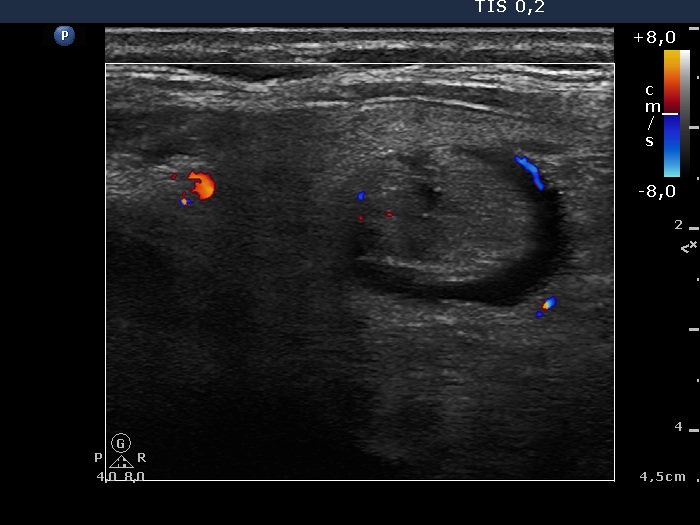

Right lobe, longitudinal scan

Left lobe, another transverse scan, color Doppler mode. This nodule presents non-specific vascular pattern.